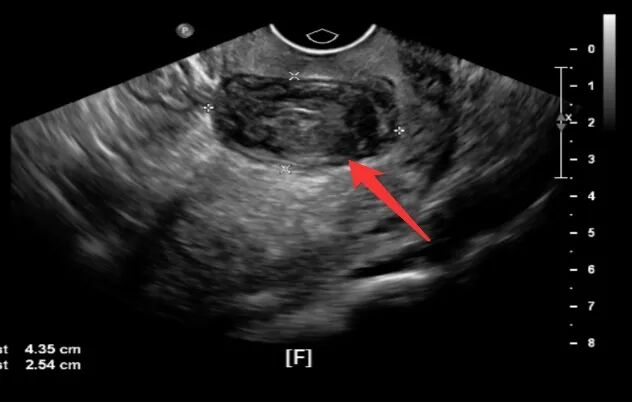

近日,一名宫颈肌瘤病史多年,要求微创手术剥除宫颈肌瘤的患者慕名来到我院妇科主任邵莉萍的专家门诊求医,她只有一个要求保留子宫…… 这位患者46岁,来我院之前已辗转多家医院,均建议切除子宫,但患者强烈要求保留子宫,故迟迟未能接受诊疗。 子宫肌瘤是女性生殖器最常见的良性肿瘤,发生于20%~40%的生育期妇女,按其生长部位可分为宫体肌瘤和宫颈肌瘤,其中宫颈肌瘤约占10%左右。宫颈肌瘤是生长在子宫颈上的肌瘤,病因主要与雌孕激素水平的增高有关。其前方与膀胱、后方与直肠、两侧与输尿管及子宫动脉关系密切,因其特殊的解剖位置,宫颈增大变形,常引起盆壁间手术操作间隙变窄,宫颈、输尿管及子宫动脉间的解剖结构发生改变,因而手术操作困难,通常采用传统的开腹手术,且多以子宫切除作为治疗宫颈肌瘤治疗的首选,很多年轻患者因此失去了宝贵的子宫。 患者入院后,邵主任带领团队结合患者病史、查体及影像检查等资料制定了周密的手术方案——宫腹腔镜联合手术剥除宫颈肌瘤。近年来,随着妇科腔镜技术的迅猛发展,宫颈肌瘤已不再是腹腔镜手术的禁忌,但腹腔镜下宫颈肌瘤剥除术对术者操作水平要求极高,如果没有认清解剖关系,没有下推膀胱或游离出输尿管,没有充分暴露术野,很可能出现膀胱、肠管及输尿管的副损伤或者导致术中术后大量出血、手术时间延长等不良事件,术者的操作技巧、手术经验及止血、缝合技术是手术成功的关键。 经过充分的术前准备,手术如期开展。邵主任带领妇科团队宫腔镜下探查宫颈肌瘤未凸向宫腔,腹腔镜探查宫颈前壁肌瘤。打开膀胱反折腹膜,下推膀胱,防止损伤膀胱。横切口打开肌瘤的包膜,在包膜内进行操作,减少临近组织及重要结构的损伤。剔除肌瘤后缝合止血,然后再次宫腔镜检查宫颈管形态如常。另外,术中发现子宫内膜息肉一枚、宫颈管粘膜下肌瘤一枚,一并予以切除,手术顺利,出血量极少,目前患者现已康复出院。 患者每一次坚定的选择,都是医院前进的动力。医护团队每一次成功的手术,都是患者选择的底气。双向奔赴的信任里,每一声谢谢,每一句放心,都是流淌在医患间的暖流。我院妇科团队熟练开展宫腹腔镜联合手术、宫腔镜子宫病损切除、宫腔镜子宫内异物取出等先进技术,为广大女性健康保驾护航。 |